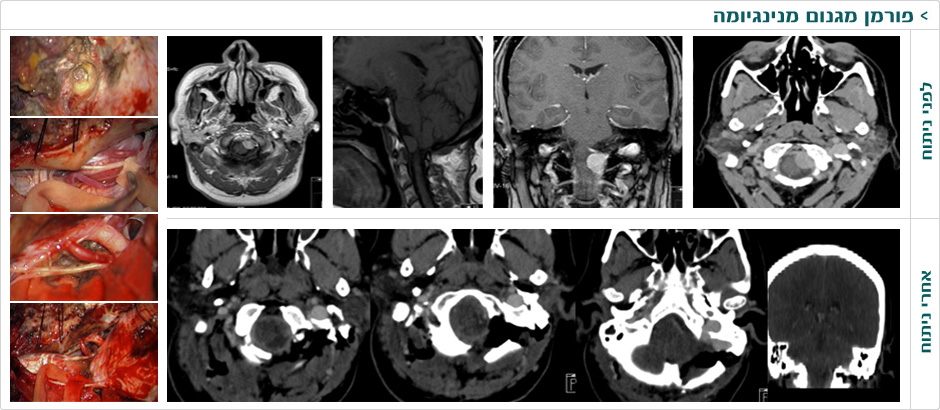

ד"ר משה עטיה – נוירוכירורג מומחה לניתוחי בסיס גולגולת ומנינגיומות